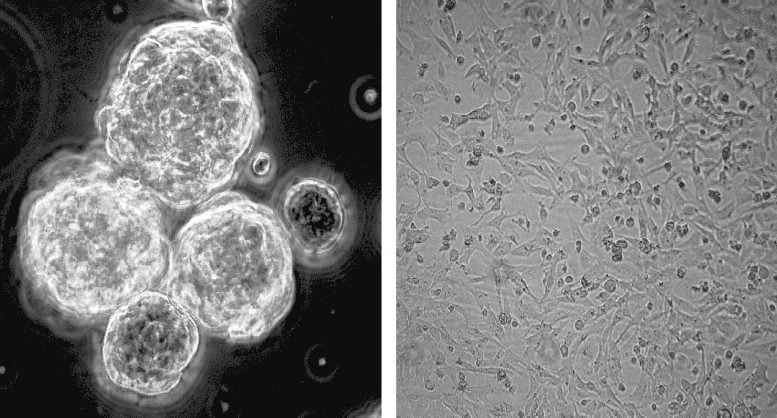

L’aggregazione di cellule tumorali nel glioblastoma senza trattamento, a sinistra, e come la niacina impedisce l’aggregazione cellulare. Credito: Per gentile concessione del laboratorio Yong.